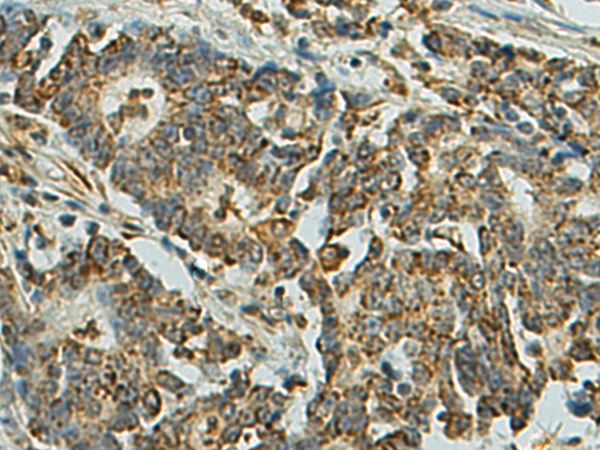

分类: 科研抗体货号: P11029别名: MLP2, MRP3, ABC31, MOAT-D, cMOAT2, EST90757应用: IHC反应种属: Human, Mouse